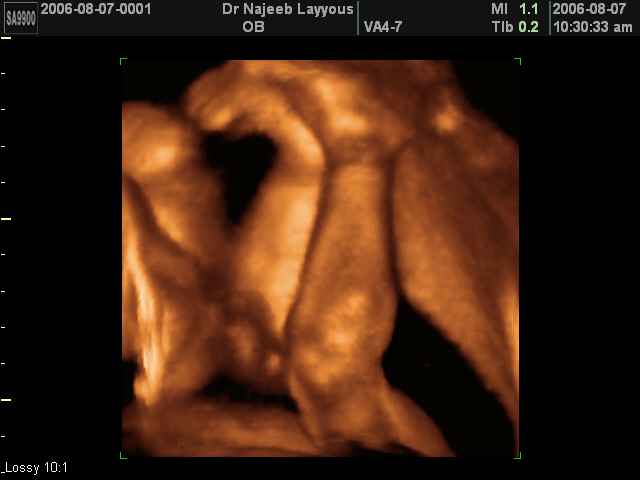

- 3D Fetal Limbs Ultrasound Scan Photos

3D Ultrasound Scan Photos of Fetal Limbs | Dr N Layyous